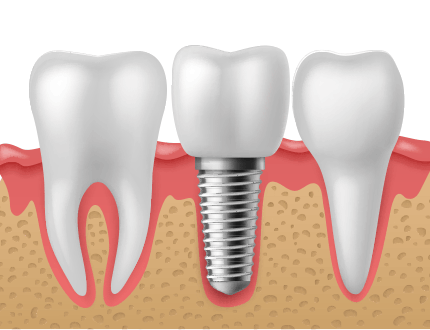

연조직, 치조골의 손상을 줄여주는 최소침습 임플란트

연조직과 치조골의 손상을 최소화하고 기타 인공물들의 사용을 최소화하여 환자의 손상에 따른 불편감을 줄여주는 최소침습 개념의 임플란트 시스템입니다. 치조골의 폭이 좁거나 상태가 좋지 않은 경우에도 골이식 혹은 골성형을 최소화하여 식립할 수 있는 최소침습 임플란트입니다.

절개하지 않는 임플란트

최소침습(무절개)방식의 임플란트

응력 분산에 뛰어난 구조

수술 후 통증과 붓기 최소화

수술 후 빠른 일상생활 복귀 가능

염증대가 없어 세균없는 구조

나사 풀림 및 파절 최소화

상황에 따른 다양한 보철물 형태